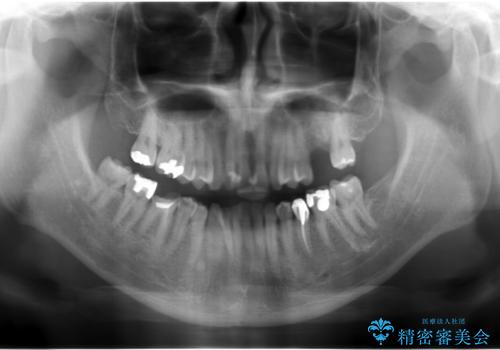

上の奥歯のインプラント、全体的な虫歯治療

- 上の奥歯が無いところにインプラントを希望して来院。

- 93万円 内訳:ストローマンインプラント(1本)62万円(静脈麻酔、再生療法、骨増生、ソケットリフト含む) 、虫歯治療(4本) 36万円 費用は治療当時の料金となります

インプラントの向かい合わせの歯や隣の歯の虫歯治療も併せて行なっています。

左上6:インプラント(ストローマン)20万円、カスタムアバットメント10万円、スクリューリテイン仮歯2万円、ジルコニアクラウン10万円、ソケットリフト10万円、マイナーGBR 5万円、静脈麻酔(麻酔認定医)5万円

左上7・左下7:PGAインレー 各6万円

左下5:仮歯 1万円、ジルコニアクラウン10万円、ファイバーコア 2万円

左下6:仮歯1万円、ジルコニアクラウン10万円